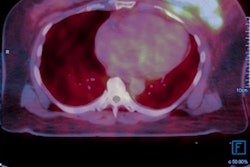

Images include high-resolution thoracic CT with no sign of pneumonia (A, B). PET/CT performed one week later, showing bilateral pneumonia with ground-glass opacities at CT (C, D), PET (E, F), and PET/CT fused images (G, H) with SUVmax of five. Maximum intensity projection (I) shows axillary nodal lesion as FDG positive. Images courtesy of Journal of Nuclear Medicine.To ensure the six cases of incidental pneumonia in March 2020 were not an aberration, the researchers compared their caseload from the same eight days of March 2019 and found only two cases (2.5%) of incidental pneumonia among 80 PET/CT studies.

Following completion of the scans, six patients (9%) showed signs of pneumonia on CT and FDG avidity in all areas of pneumonia, which made these patients suspicious for COVID-19. The six patients included four women, between 55 and 65 years old, and two men, ages 65 and 77, respectively. When physicians followed up with reverse transcription polymerase chain reaction (RT-PCR) tests, five patients (83%) were confirmed to have COVID-19.